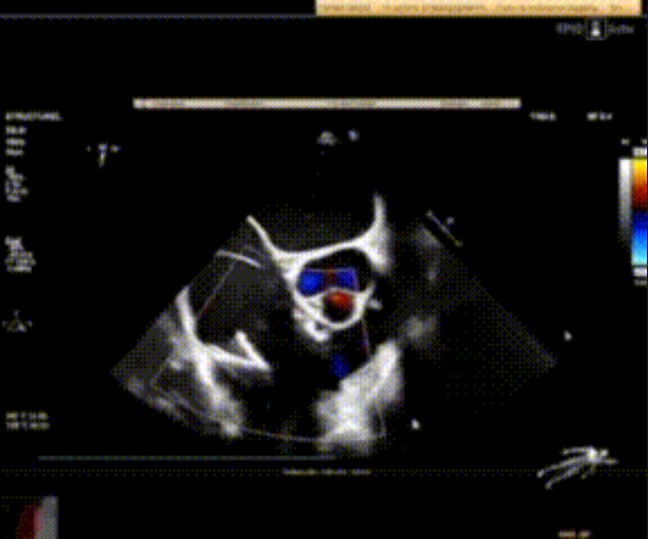

術前心臟超聲提示:極重度三尖瓣返流,右房容積明顯增大,三尖瓣瓣環顯著擴張。

術后心臟超聲提示:LuX-Valve Plus植入后,三尖瓣瓣環處可見人工瓣膜回聲,未見返流,人工瓣膜穩定,瓣葉開閉良好,連續多普勒估測三尖瓣平均跨瓣壓差僅為1mmHg。